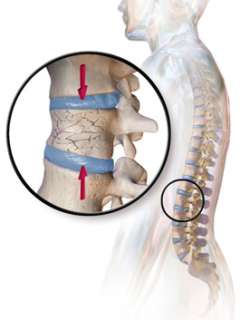

Osteopenia, osteoporosis, or fractures – caused by abnormal removal of calcium from bones, can also cause bony pain / muscle pain

Does Osteoporosis Cause Bone Pain or Achy Joints?

It is a common misconception that osteoporosis usually causes bone pain. In fact, most people have no symptoms unless there is a fracture. So a person can be completely free of pain and still have osteoporosis. Vertebral fractures (in the spine) can also be painless but cause progressive loss of height over time.